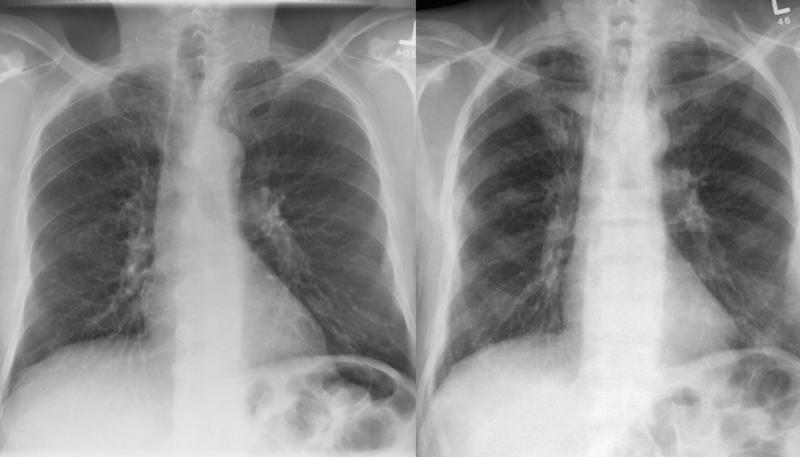

Gallery Lung Cancer Mets Prostate before and after

Prostate before and after